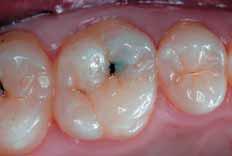

Two different operators performed the clinical procedures. Class I restorations were of small dimensions and did not have to involve functional areas. Only if a preliminary occlusion check excluded that the cavity preparation would extend to functional areas was the patient included in the study. Following anesthesia, rubber dam was placed, all carious structures were excavated, and any restorative material was removed. Preparation was performedusing conventional diamond burs in a highspeed hand piece, with no bevel on margins. The preparation design was dictated by the extent of decay. After the complete excavation of the carious lesion, and before applying the restoration, the occlusion was again checked in order to definitively exclude the possibility that the restoration could be placed in direct functional areas. The teeth were restored following manufacturer’s instructions. A small amount of Vertise Flow was applied into the cavity with the included dispenser tip. This first thin layer (no more than 0.5mm in thickness) was brushed on the cavity surfaces for 1520s. After brushing, a 20s polymerization was performed with a DEMI LED light curing unit (Kerr, Orange, CA, USA). Then, the

cavity was filled in bulk unless the thickness of the single increment would exceed the limit for effective polymerization. In the latter case the cavity two layers had to be stratified and singularly cured to fill the cavity. Following an additional 20s polymerization, the filling was contoured using 12- Blade Carbide Burs and 40μm-grit Diamond Burs. Then, the restoration surface was finished with Carbide Burs at 30 Blades and 20μm-grit Diamond Burs. Final polishing was performed with Opti1Step Polisher (KerrHawe, Bioggio, Switzerland). The restorations were placed in the time period between January and March 2009, and examined at baseline, after 1 day, 1 week, 1 month, 3 months, and 6 months by a different operator who had been blinded with regard to the restorative material used. At each recall, data regarding post-operative sensitivity, stability and longevity were collected with reference to the Ryge criteria.36 Postoperative sensitivity, was assessed as the patient comfort with the restoration under function, cold and warm stimuli, and a gentle air stream. Sensitivity was defined by a scale from 0-10, as described above. The other evaluated clinical parameters were: marginal discoloration and integrity, secondary caries, fracture, vitality test, retention and interproximal contacts.

Pre-operative view.First layer placement.Brushing for 20s.

20s polymerization of the first layer.Cavity fill-up.First layer placement of the second restoration.

Table6: Performance criteria according to Ryge. For post-operative sensitivities, mean value and standard deviation is provided (1 = lowest sensitivity, 10 = highest sensitivity) Class I restoration performed with Vertise Flow.

Opti1Step PolisherRestorations after contouring-finishing-polishing.6 months follow